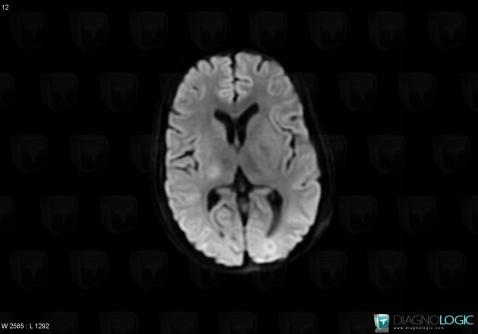

Toxoplasmosis, Cerebral hemispheres, Basal ganglia and capsule, MRI

Here is the specific information in the key image above:

- Diagnosis Toxoplasmosis (link to Abscess), Location(s) Basal ganglia and capsule, with gamuts DWI hyperintense lesionCerebral hemispheres, with gamuts DWI hyperintense lesion